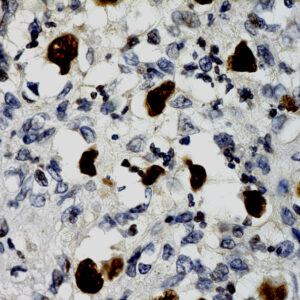

BioGenex offers fluorescein-labeled oligonucleotide probes to detect DNA or RNA using In situ Hybridization (ISH). These probes allow quantitative detection of specific DNA/RNA sequences in their native form within the cells of formalin-fixed paraffin-embedded (FFPE) tissue sections. These probes offer reliable, highly sensitive, and easy-to-perform DNA and RNA ISH assays when used with the BioGenex ISH Detection Systems.